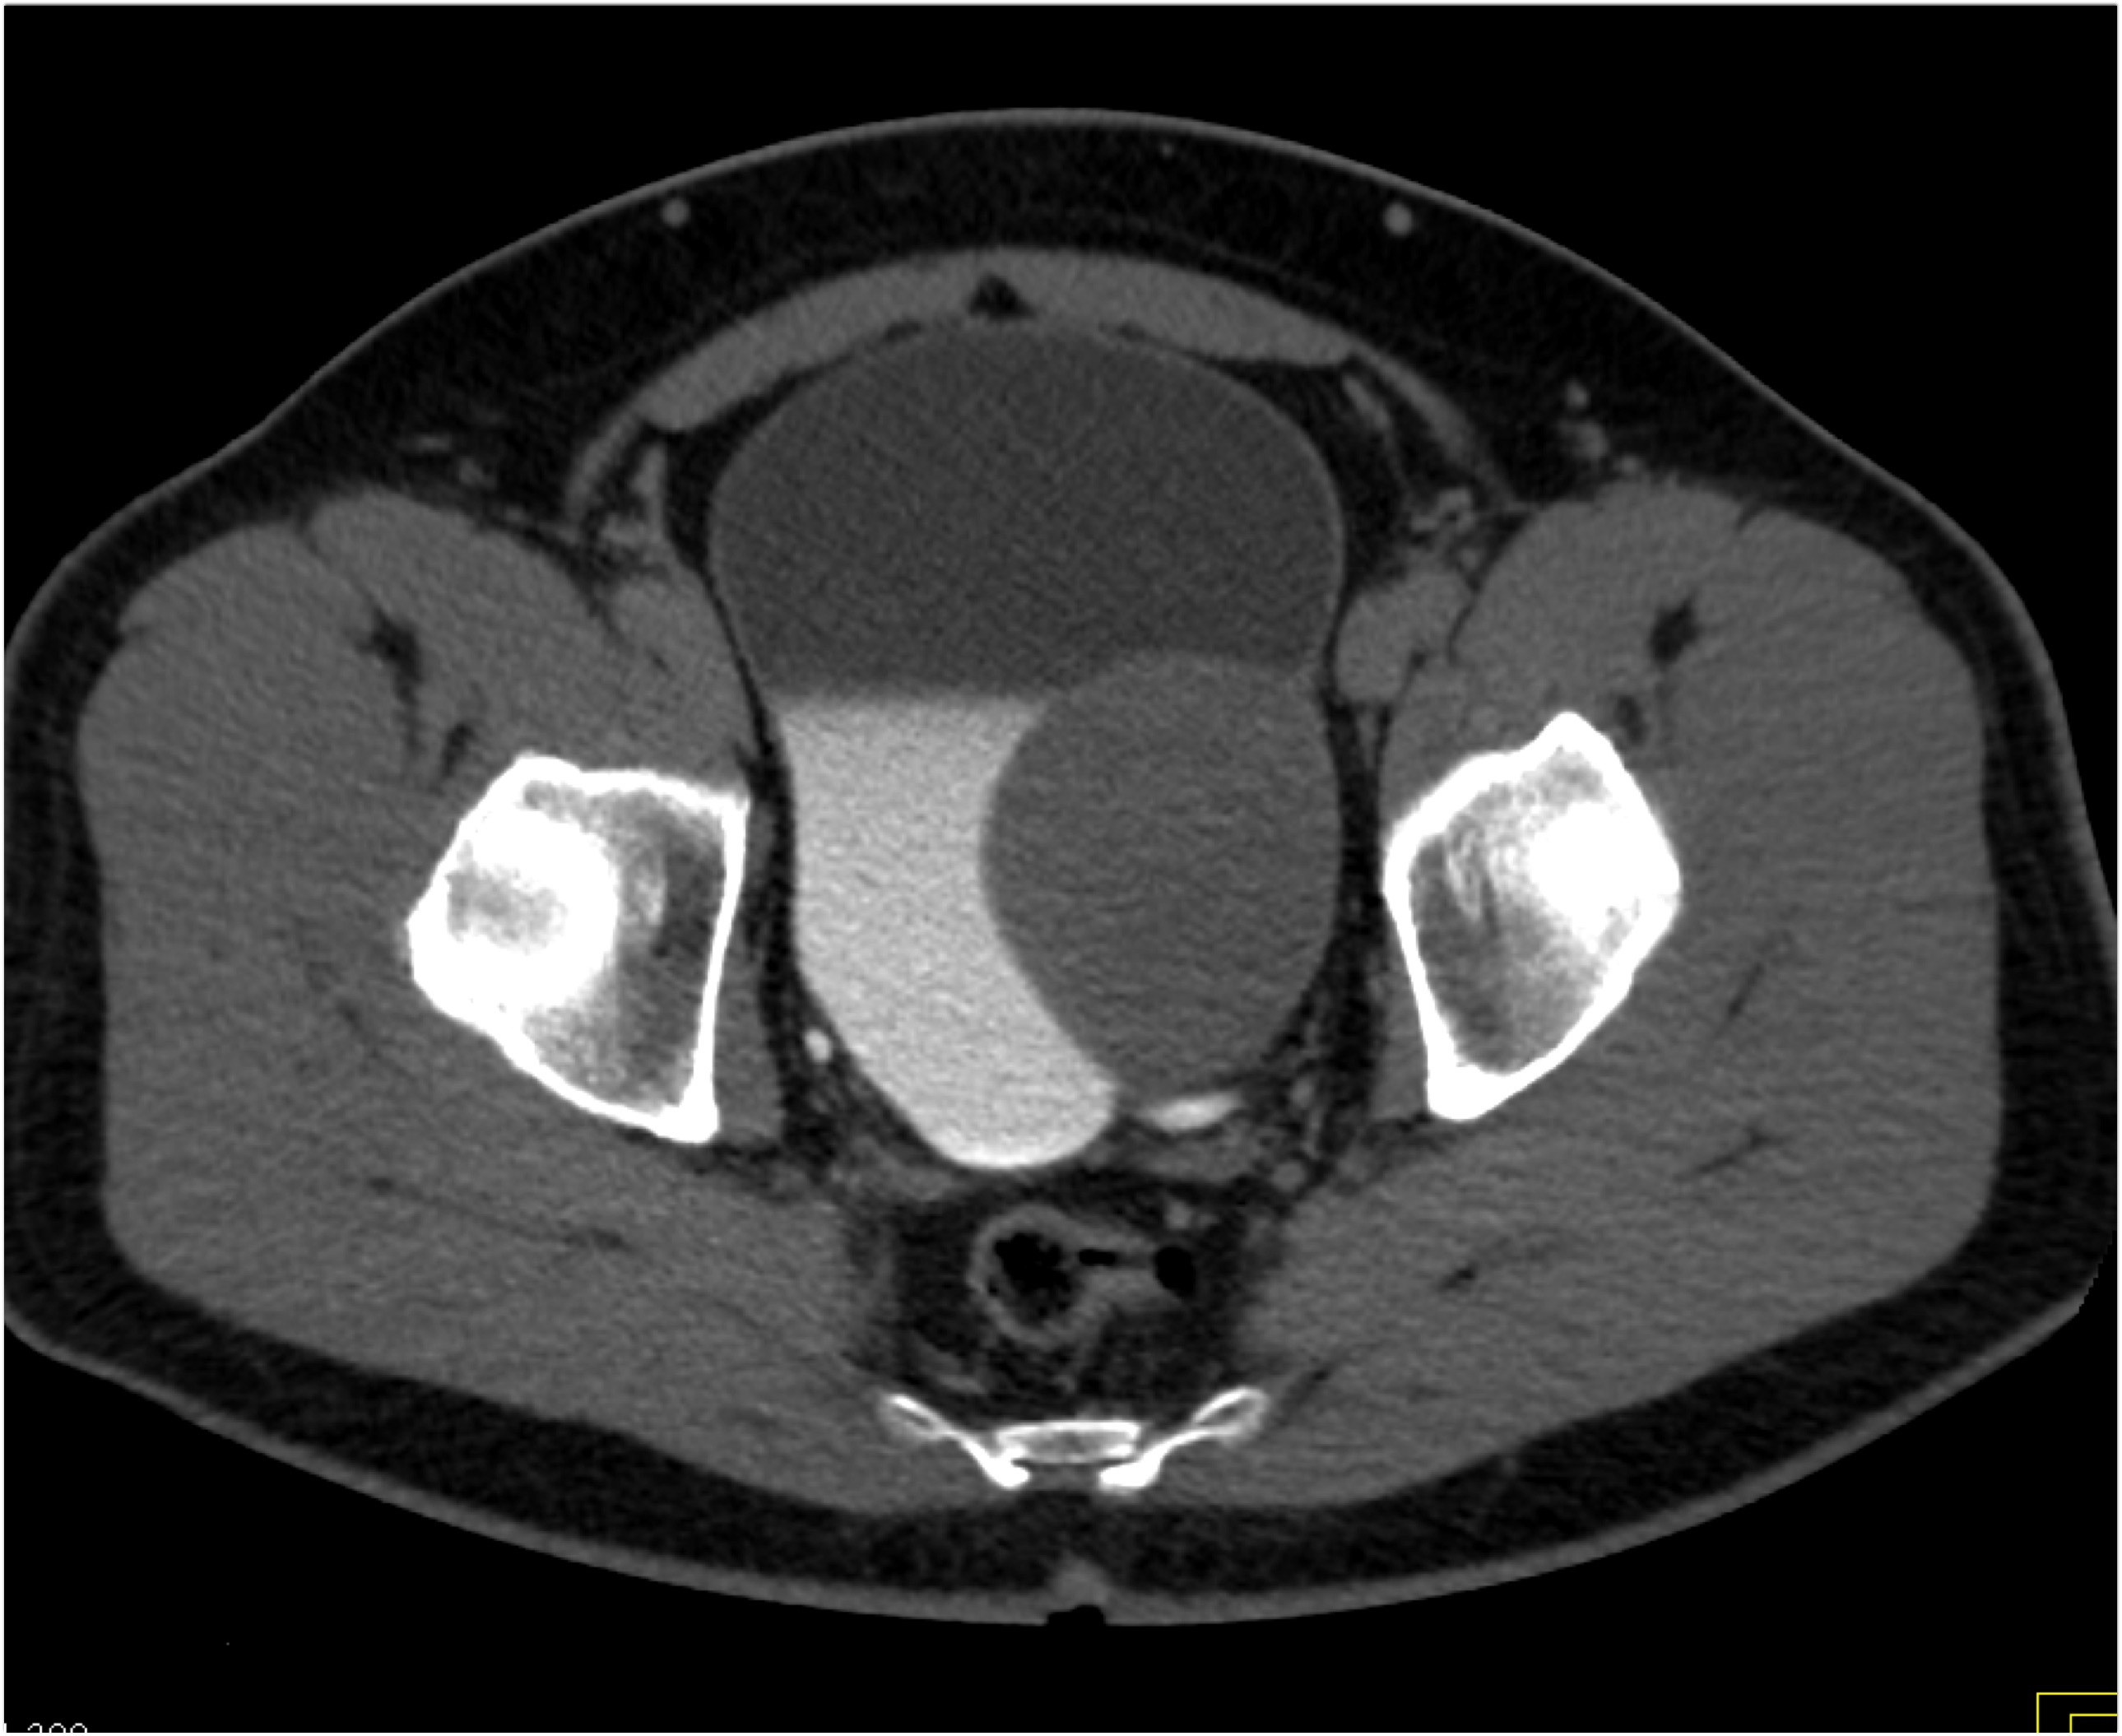

2) In this patient on dialysis for ESRD the best diagnosis is?

AV fistulae with aneurysms